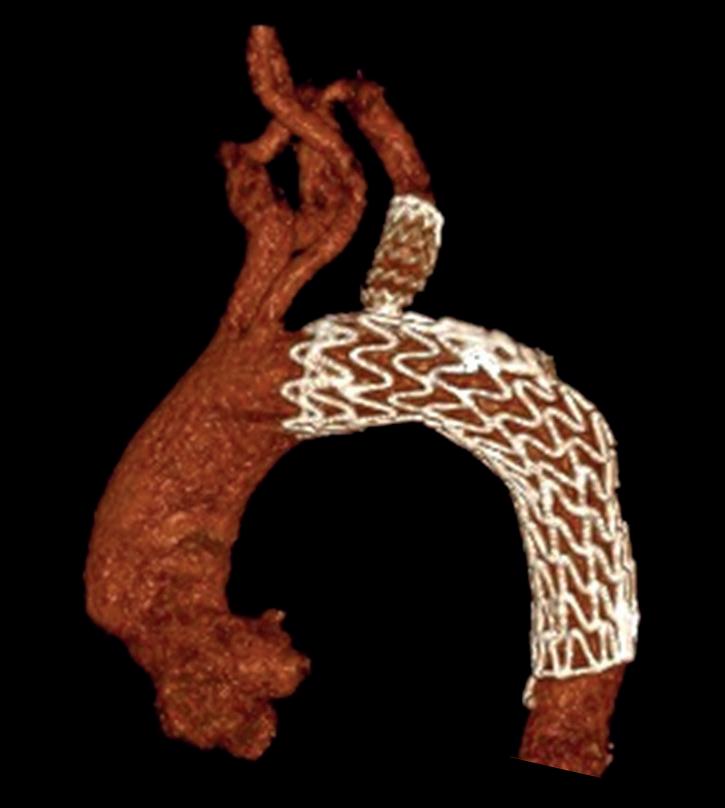

Left: Pre- and postoperative images (courtesy of Dittmar Böckler) of the first European implantation of the Gore Tag TBE; above: Dittmar Böckler performing the implantation